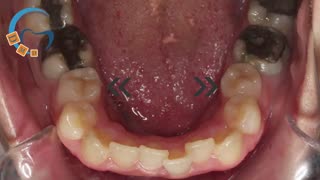

ارتودنسی ثابت و متحرک نامرتبی دندانی و دیپ بایت شدید بدون کشیدن دندان